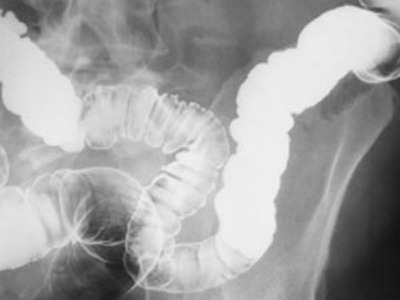

Elk van de vijf elementen (Vuur, Aarde, Metaal, Water, Hout) is herkenbaar door verschillende kenmerken. Metaal is … seizoen, temperatuur, smaak, opening, paleis, opslag, emotie, vorm. Metaal is … herfst, droogte, scherp, neus, dikke darm, longen, vertrouwen, kantoor, ovaal.